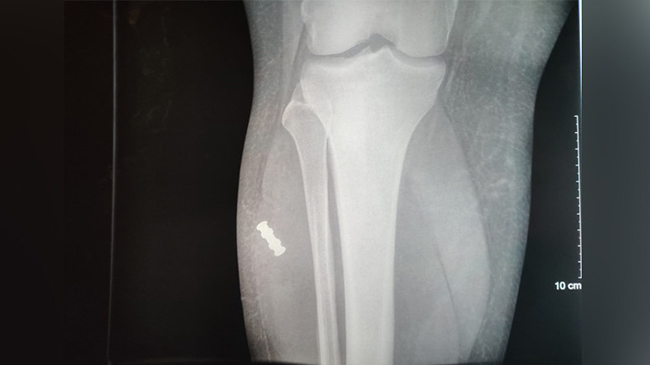

Parmi les personnes blessées, RT France a contacté le photographe de presse Mohammed Taha, touché à la jambe lors de cette violente confrontation entre pompiers et forces de l'ordre à Paris au mois de janvier. Un objet métallique enveloppé dans une matière plastique est venu se ficher dans la jambe du journaliste lors de l'explosion d'une grenade ce jour-là. La blessure lui a valu trois semaines d'interruption temporaire de travail. L'objet en question ressemble très fortement à une pièce qui compose la grenade GM2L du fabricant français Alsetex.

En l'occurrence, il s'agirait de la «composition retard pour initier le réservoir au sol» [14 sur le plan de coupe], une pièce métallique donc, emballée dans un «bouchon porte retard» [11 sur le plan de coupe] en matière souple polymère qui n'apparaît pas sur l'imagerie médicale ci-dessus, mais qui était également bien présente dans la jambe de Mohammed Taha.